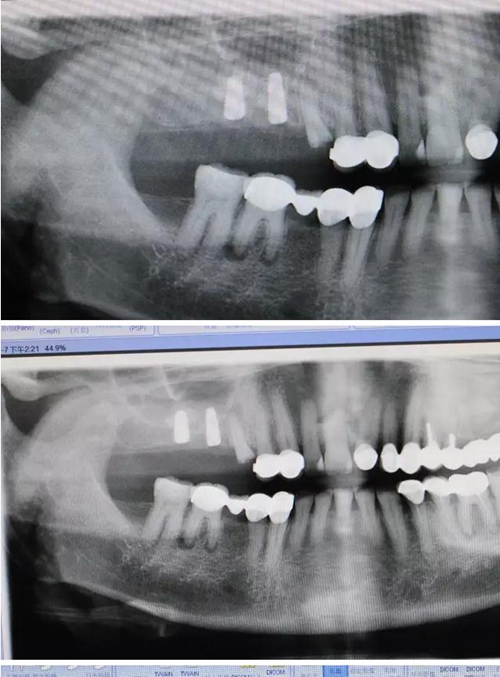

【病例分享】右上內(nèi)提+5冠延長(zhǎng)1 梁光強(qiáng)